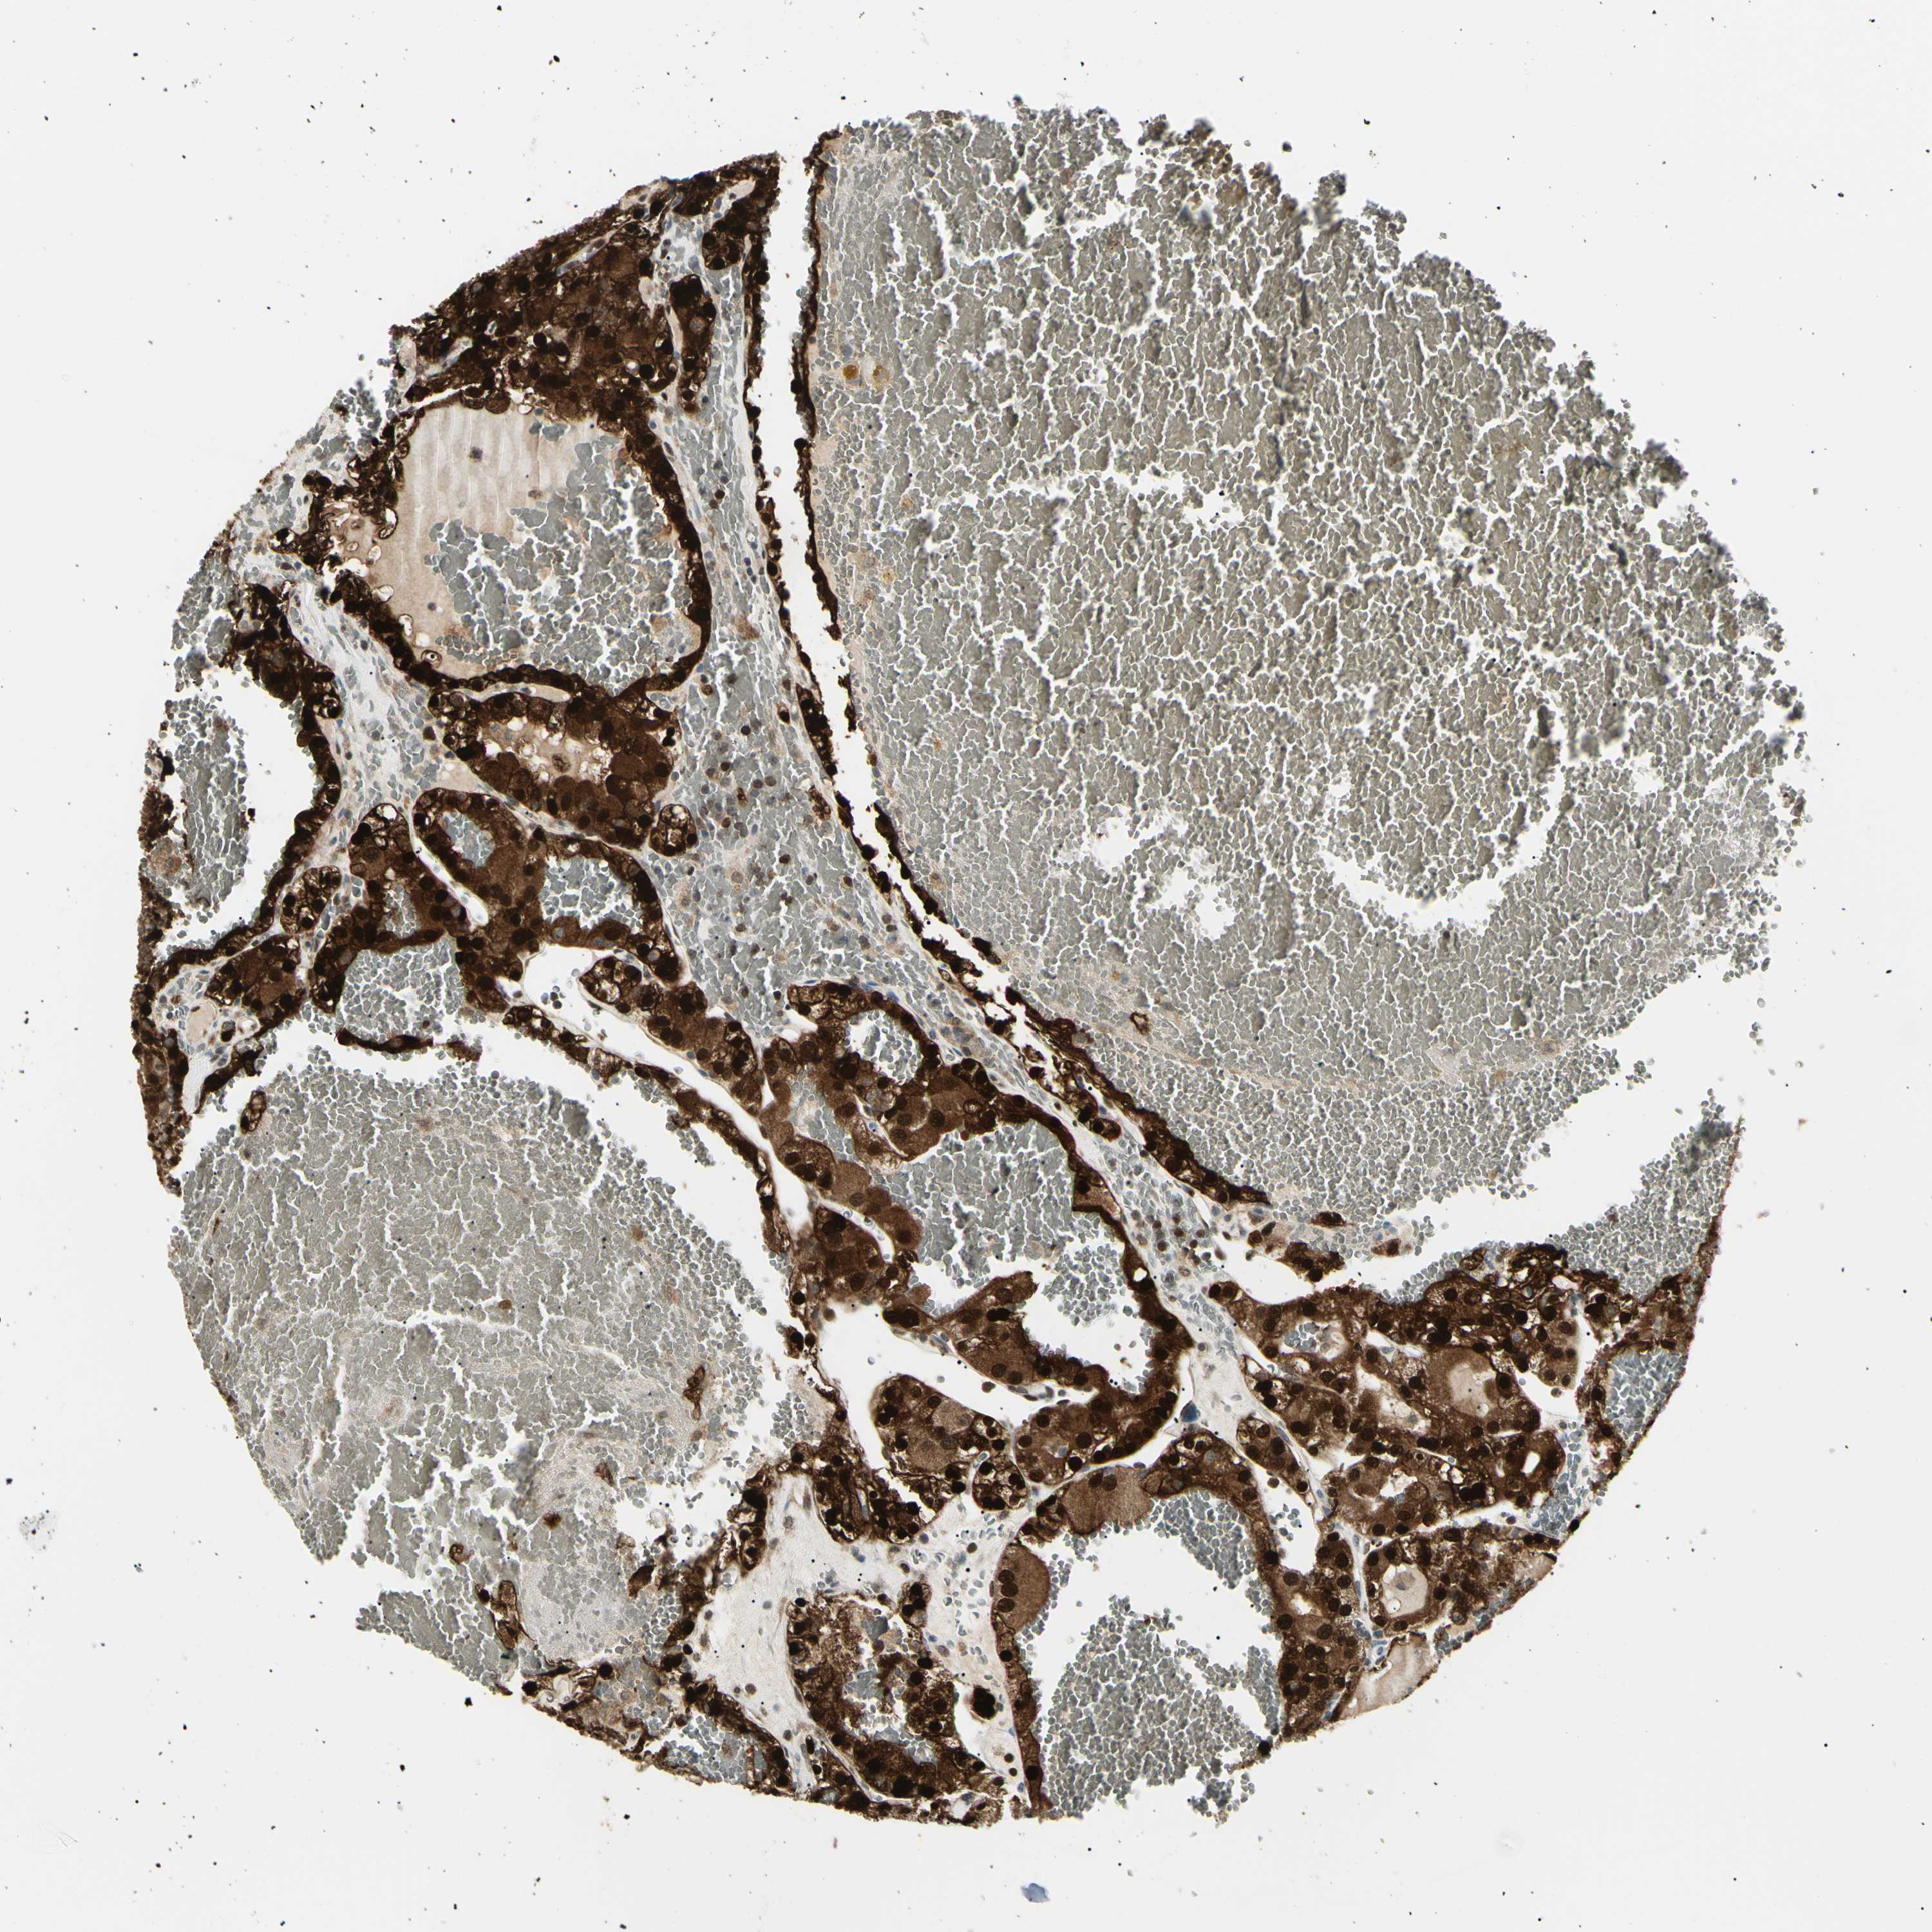

CANCER RENAL CANCER Show tissue menu

KICH TCGA KIRC TCGA KIRC VALIDATION KIRP TCGA PROTEIN RCC CPTAC PROTEIN EXPRESSION